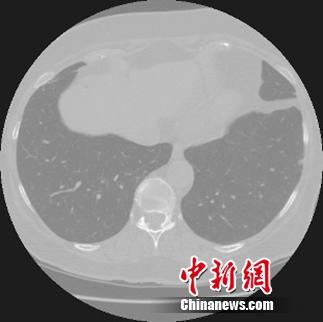

阿里云啟動天池醫療AI大賽挑戰早期肺癌診斷。